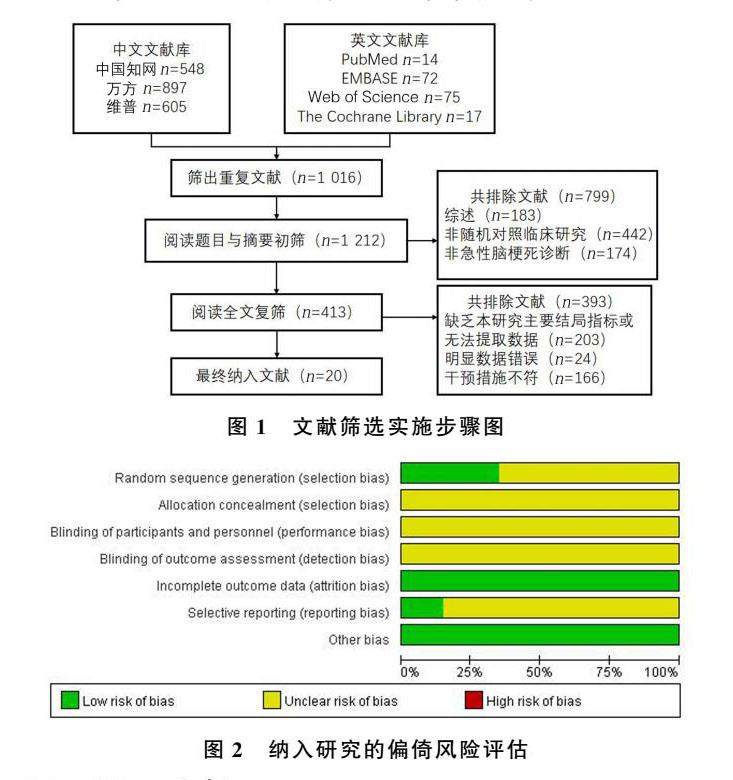

论著 | 高压氧治疗急性脑梗死效果的Meta分析

论著 | 高压氧治疗急性脑梗死效果的Meta分析